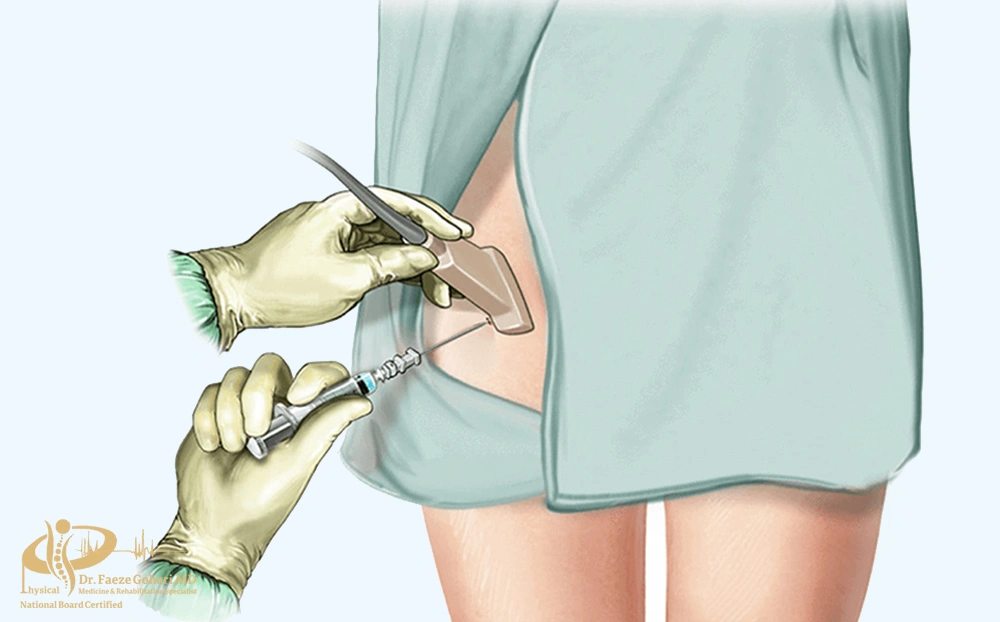

لگن و دنبالچه

بلوک عصبی لگن و دنبالچه

در تصویربرداری زنده هنگام بلوک عصبی دنبالچه میتوان محل ورود سوزن و تزریق ماده بیحسی و بلاککننده عصب را مشاهده کنید.

در مواردی که درد ناحیه لگن یا دنبالچه به درمانهای معمولی مانند دارو، فیزیوتراپی یا تغییر سبک زندگی پاسخ ندهد و مزمن شود، پزشک ممکن است بلوک عصبی را تجویز کند. این روش با تزریق دارو در اطراف اعصاب درگیر، انتقال پیام درد را مهار میکند و به بیمار فرصت میدهد تا درد کاهش یافته و کیفیت زندگی و توانایی انجام فعالیتهای روزمره بهبود یابد.

نحوه انجام بلوک عصبی لگن و دنبالچه

بلوک عصبی لگن و دنبالچه روشی کمتهاجمی است که با تزریق داروی بیحسی (معمولاً همراه با کورتون) اطراف اعصاب هدف انجام میشود تا انتقال پیام درد به نخاع و مغز قطع یا کاهش یابد. این کار معمولاً تحت هدایت تصویربرداری (فلوروسکوپی یا سونوگرافی) صورت میگیرد تا ایمنی و دقت بالا برود.

- آمادهسازی و استریل: بیمار در وضعیت مناسب (نشسته یا خوابیده به شکم) قرار میگیرد، پوست ناحیه ضدعفونی و پوشش استریل اعمال میشود.

- تعیین مسیر ورود سوزن: پزشک با کمک فلوروسکوپی (اشعه ایکس زنده) یا سونوگرافی مسیر ایمن برای رسیدن به اعصاب لگن یا دنبالچه را مشخص میکند.

- بیحسی سطحی پوست: قبل از ورود سوزن اصلی، پوست و بافت سطحی با مقدار کمی داروی بیحسی موضعی بیحس میشود.

- وارد کردن سوزن: سوزن باریک تحت هدایت تصویربرداری به نزدیکی اعصاب هدف (مثل اعصاب ساکرال، پودندال یا کاکسیژیال) پیش برده میشود.

- کنترل ایمنی: پیش از تزریق دارو، پزشک با کشیدن پیستون سرنگ (آسپیراسیون) مطمئن میشود سوزن داخل رگ قرار نگرفته است. در برخی موارد مقدار کمی ماده حاجب تزریق میشود تا محل دقیق پخش دارو تأیید گردد.

- تزریق دارو: داروی بیحسی همراه یا بدون کورتون بهتدریج تزریق میشود تا اطراف عصب پخش گردد.